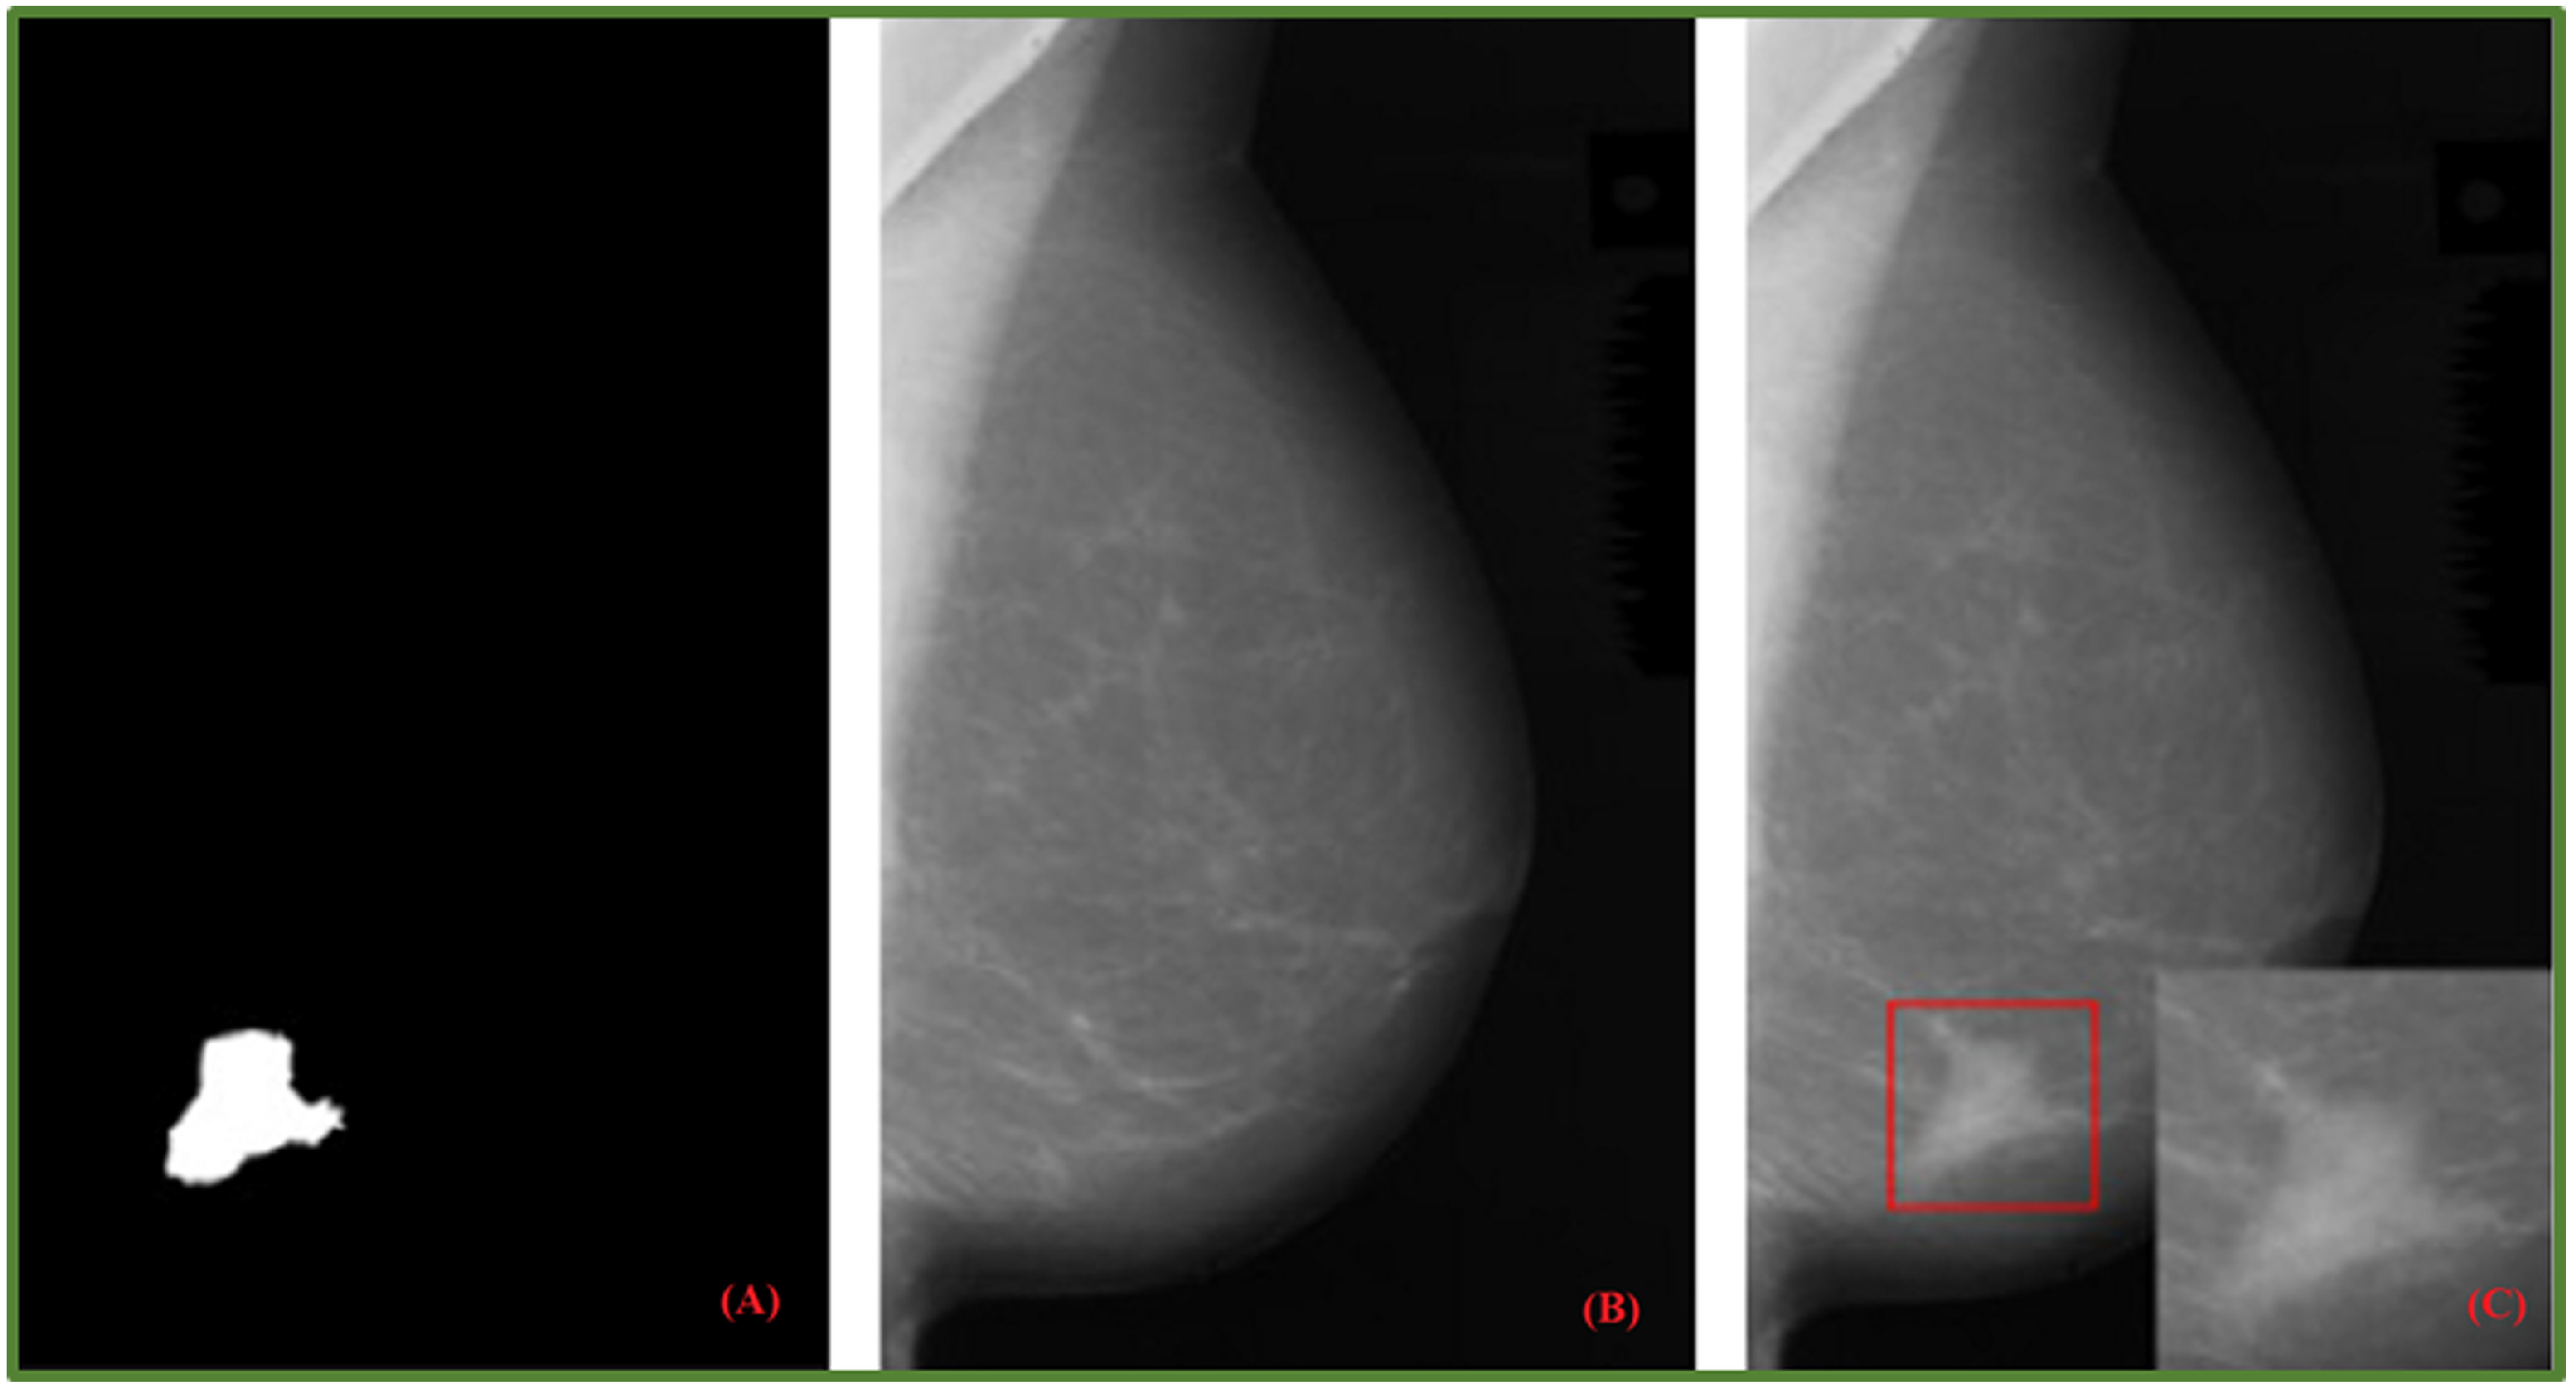

- Costa, A.C.; Oliveira, H.C.; Vieira, M.A. Data augmentation: Effect in deep convolutional neural network for the detection of architectural distortion in digital mammography. In Proceedings of the Brazilian Congress on Medical Physics, Santos, Brazil, 21–24 August 2019. [Google Scholar]

- Min, H.; Wilson, D.; Huang, Y.; Liu, S.; Crozier, S.; Bradley, A.P.; Chandra, S.S. Fully automatic computer-aided mass detection and segmentation via pseudo-color mammograms and mask r-cnn. In Proceedings of the 2020 IEEE 17th International Symposium on Biomedical Imaging (ISBI), Iowa City, IA, USA, 3–7 April 2020; pp. 1111–1115. [Google Scholar]